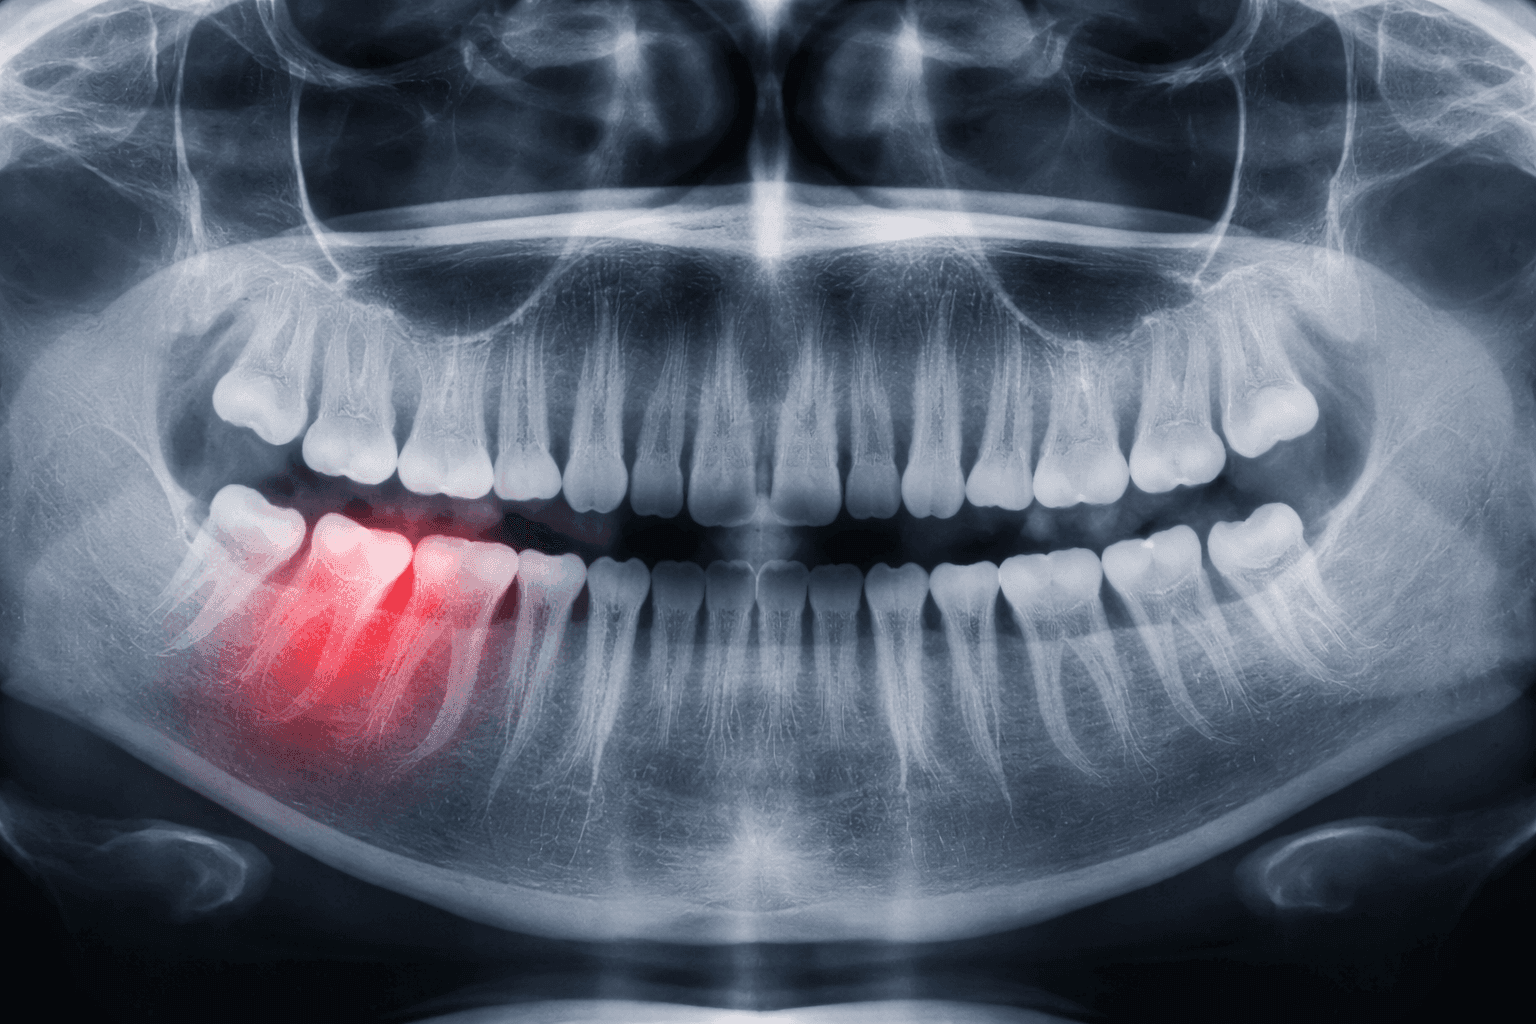

Немаловажно здесь и то, что зуб мудрости появляется в труднодоступном месте (у самого края челюсти вверху или внизу). Он не входит в основную «комплектацию» и является дополнительным. Для него природой попросту не предусмотрено специального пространства, за счет чего его появление влечет за собой сдавливание соседних моляров. На почве этого возникает острое ощущение дискомфорта, как будто весь зубной ряд смещается в сторону.

Особенно ощущается присутствие во рту «постороннего» при неправильном его положении, когда он растет по направлению вправо или влево, а не вверх. Несладко приходится и тем, у кого «восьмерка» прорезалась лишь наполовину или даже меньше, и дальше показываться не хочет. В этом случае возможны ощутимые боли в десне, отдающие в ухо, горло или голову.

Чаще всего лишний моляр появляется в нижнем ряду. В этом случае боль заметно сильнее, чем при его прорезывании вверху. Это связано с тем, что последний реже отклоняется от «курса развития» и почти никогда не упирается в соседние зубы. Так снижается риск нарушения целостности десны, появления ее кровоточивости и неприятных ощущений. В случае же с нижним моляром костная ткань может воспаляться и доставлять существенные неудобства при приеме пищи.